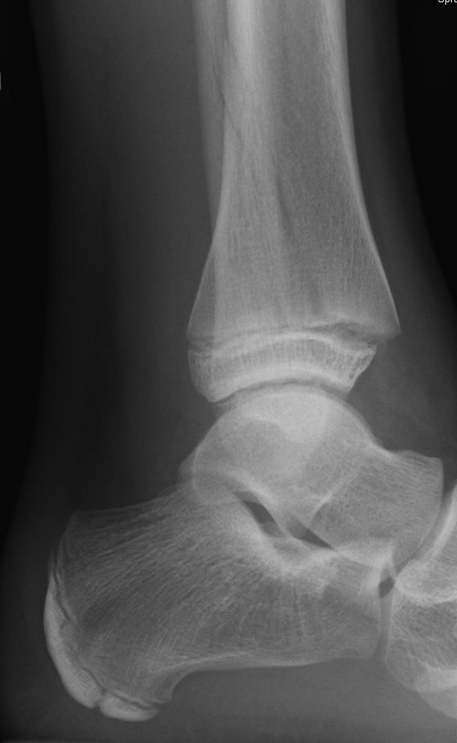

Röntgen

Die Standard Röntgendiagnostik des Sprunggelenks umfasst Bilder in anteriorposterioren (a.p.) und im seitlichen Strahlengang 6. Für die exakte Abbildung des Innenknöchels müssen beide Malleolen parallel zur Röntgenplatte zu liegen kommen. Je nach Torsion der Tibia macht dies eine Innenrotation des Fußes zwischen 10° und 30° erforderlich (Abb. 3).

Manchmal sind mediale Malleolarfrakturen nur in einer der Aufnahmen in ihrem Ausmaß erkennbar. Keine Rolle spielt die gehaltene Aufnahme beim Kind, insbesondere bei der akuten Verletzung. In seltenen Fällen hat dieses Verfahren bei Verdacht auf eine chronische Instabilität eine Berechtigung.